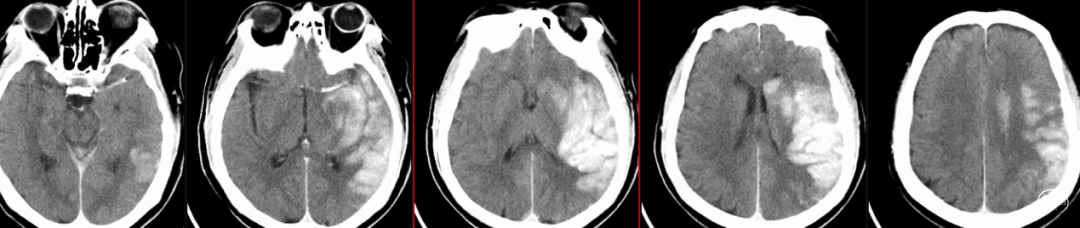

头颅CT(12/3):左侧颞叶可以低密度影,左侧大脑中动脉可疑高致密征。

头颅CTA(12/3):左侧大脑中动脉闭塞。

术后第1天复查头颅CT:左侧基底节及颞叶顶叶造影剂渗出改变。

术后第2天复查CT:造影剂吸收。

术后4天复查CT:左侧颞叶顶叶梗死,部分渗血改变可能。

术后复查CTA:提示左侧大脑中动脉通畅,支架在位。